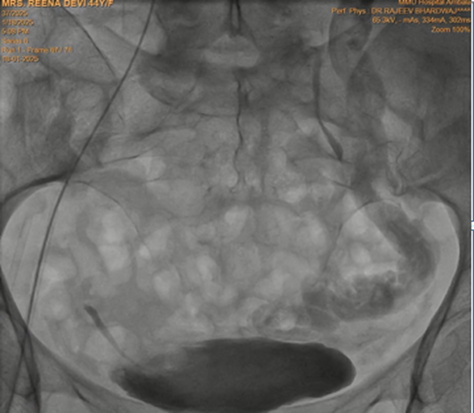

Keeping in view the possibility of Nutcracker syndrome (NKS). patient was taken up for percutaneous treatment. Right femoral vein puncture was done. Femoral vein angiography was done to see inferior vena cava (IVC), (Fig.1) to have idea of origin of left renal vein. Femoral artery access was also taken and left renal arteriography was done to trace renal vein in venous phase, but it could not be visualised. Since renal vein was not visualised, blind entry was done with terumo wire passed through right Judkins (JR)catheter. Catheter was then negotiated into LRV and venography was done (Fig. 2). It showed markedly dilated left gonadal vein (LGV), and left ovarion vein (Fig 3). Hardly any contrast was entering into IVC, due to compression by superior mesenteric artery (SMA). It was decided to put a stent in LRV across the compressed segment. To properly define the site of obstruction and stent placement, a JR catheter was placed in SMA (Fig 4), from left brachial artery approach. Self-expanding venous stent was then deployed, size 14x 60 mm. (Fig 5). LRV angio was then done which showed free flow of contrast into IVC and minimal reflux into LGV (Fig. 6). If, large reflux persisted, then coiling of LGV would have been required.

Figure 2: Left renal venography shows hugely dialted gonadal vein, with very little flow into inferior vena cava (Due to renal vein compression and reflux of blood into gonadal vein)

Figure 3: Marked dilatation of left ovarian vein, due to reflux from gonadal vein.